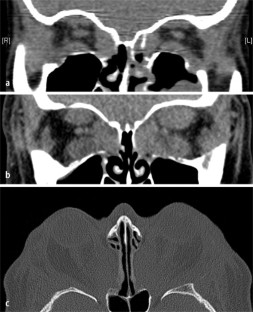

Abb. 1

Abb. 2

Abb. 3

Abb. 4

Abb. 5

Abb. 6

Abb. 7

Abb. 8

Abb. 9